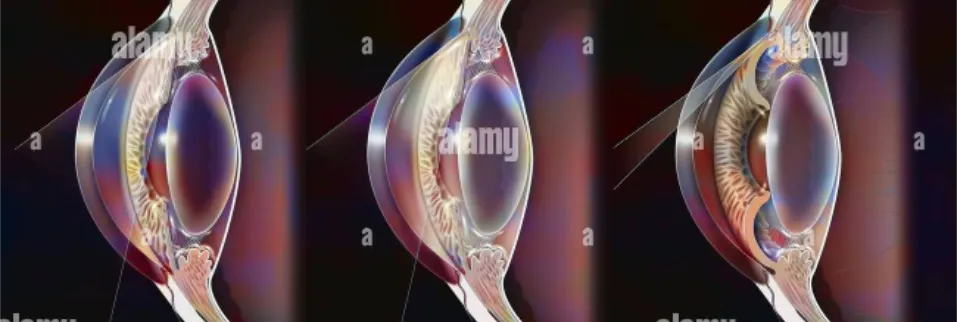

Glaucoma types vary depending on the integrity of outflow channels and in how they impact eye pressure and optic nerve health. Some forms, like open-angle glaucoma, progress slowly and silently over time, while others, such as angle-closure glaucoma, can cause sudden, painful vision loss. Each type requires a tailored approach to diagnosis, monitoring, and treatment to prevent irreversible damage. Understanding these differences is essential, as early-stage glaucoma often goes unnoticed until significant damage has occurred. Regular comprehensive eye exams play a crucial role in detecting the specific type of glaucoma early, enabling timely intervention to protect vision.

Primary Open-Angle Glaucoma

Primary open-angle glaucoma is the most common type of glaucoma and typically develops slowly over time. It occurs when the eye’s drainage canals become less efficient due to sclerosis of drainage system, leading to a gradual buildup of intraocular pressure. This pressure damages the optic nerve without causing noticeable symptoms in the early stages. Because of its silent progression, vision loss often goes undetected until it becomes more advanced. Regular eye examinations are essential to identify and manage this condition early.

Angle-Closure Glaucoma

Angle-closure glaucoma is a less common but more acute form of the disease. It occurs when the drainage angle of the eye becomes suddenly and completely blocked, causing a rapid rise in intraocular pressure. This can lead to severe eye pain, headache, nausea, and sudden vision loss. Because it progresses quickly, it is considered a medical emergency and requires immediate treatment. Prompt diagnosis is crucial to prevent permanent vision damage.